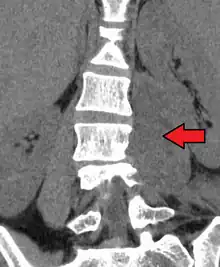

Psoas abscess is a collection of pus (abscess) in the iliopsoas muscle compartment.[1][2] It can be classified into primary psoas abscess (caused by hematogenous or lymphatic spread of a pathogen) and secondary psoas abscess (resulting from contiguous spread from an adjacent infectious focus).[2]

Psoas abscess may be caused by lumbar tuberculosis, vertebral osteomyelitis, and pyelonephritis. Patients with Crohn's disease, diabetes, or immunocompromised states are at a higher risk of developing a psoas abscess.

Symptoms include flank pain, fever, and an inguinal mass. A positive psoas sign should raise suspicion of psoas abscess as a possibility. Owing to the proximal attachments of the iliopsoas, such an abscess may drain inferiorly into the upper medial thigh and present as a swelling in the region. The sheath of the muscle arises from the lumbar vertebrae and the intervertebral discs between the vertebrae. The disc is more susceptible to infection, from tuberculosis and Salmonella discitis. The infection can spread into the psoas muscle sheath.[3]